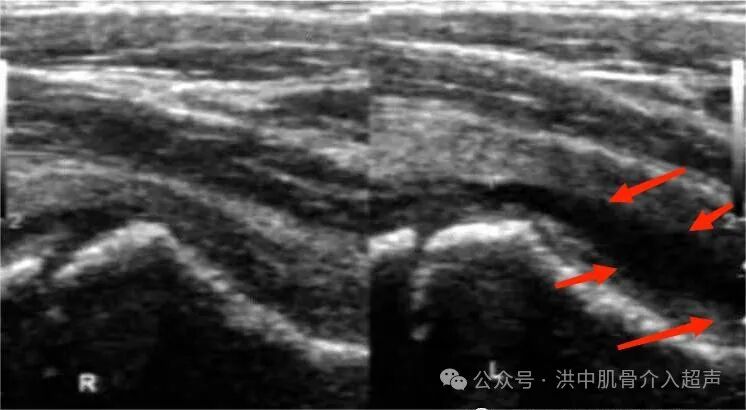

彩超诊断髋关节滑膜炎可分为关节囊肿胀型和关节腔积液型。

关节囊肿胀型:患侧股骨颈颈前间隙较健侧增宽大于1mm,或者整个关节囊(箭头所示)厚度大于5-7mm,内回声欠均匀,关节囊与髂腰肌之间的界面凸面向前(正常为凹面向前)。